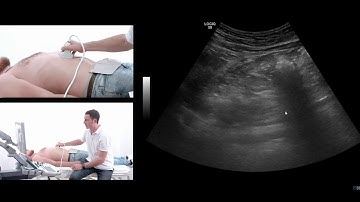

Is that My Pancreas!? Interpret a Live Ultrasound Scan with Us! 🖥️ #ultrasound #letslearn